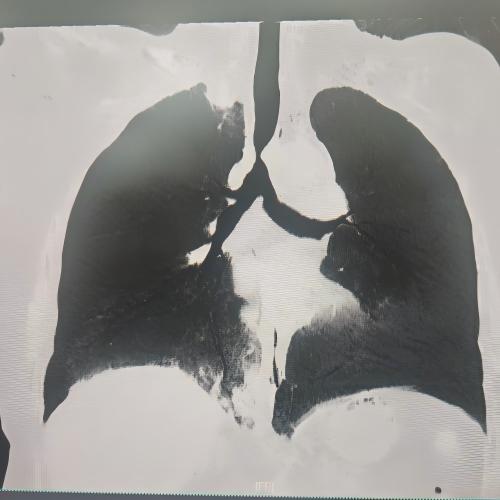

患者为75岁女性,因“反复咳嗽咳痰、气促10余年,加重3月”,于3月3日入住湘雅三医院呼吸与危重症医学科。入院时患者呼吸困难症状严重,CT检查提示气道存在严重狭窄,随时面临窒息风险。经管床医生杨红辉副主任医师评估,患者气管狭窄情况复杂:最狭窄处管腔直径仅剩1-3mm,科室最细的4.0mm支气管镜也无法通过;狭窄位置极低,下缘距隆突仅1.6cm,意味着无法通过气管切开绕过病灶;狭窄处周围组织的CT值高达60-70Hu且无强化,因而直接植入支架存在无法撑开或加重堵塞的风险;同时,患者无法耐受全身麻醉,仅能采用利多卡因进行表面麻醉,操作难度较大。

方案确定后,ICU团队为何智辉、邢伟、邓龙天为患者建立体外生命通道;呼吸介入团队孟婕、杨红辉、刘建明、邹丽君、贺一峻等通过球囊对狭窄部位进行预扩张,随后在距隆突仅1.6cm的低位气道精准植入支架。支架贴合良好,气道顺利开通,全程操作约1.5小时。患者当晚撤离ECMO,次日从ICU转回普通病房。后续肺泡灌洗液检测显示,患者大气道狭窄的原因为气管结核导致的瘢痕性狭窄。